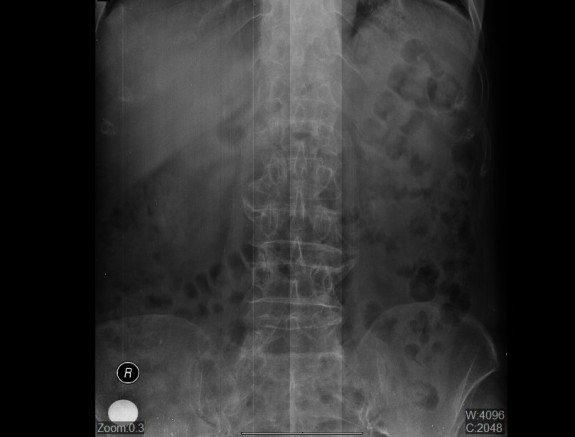

Operativni tim su sačinjavali mr sc. dr Nikola Bojić, mr sc. dr Zoran Bjelogrlić, dr Milorad Maran, dr Haris Vehabović, dr Ljubiša Tomić, dr Sanja Jeličić, instrumentari Raca Mira, Tomašević Goran i Lukić Dijana. Kompresivni prelomi pršljenskih tijela nastaju kao posljedica slabljenja njegove građe odnosno gubitka koštanog tkiva što rezultira smanjenom čvrstinom. Najčešći uzrok ovih promjena je osteoporoza. Ovakvi prelomi pršljenskog tijela su prvi klinički znak osteoporoze. Isto tako ukoliko su pršljenska tijela zahvaćena metastazama malignih tumora ili benignim tumorima krvnih sudova dolazi do razaranja koštanog tkiva. U tako izmjenjenim uslovima, moguće je da pri minimalnim traumama kao što su pokreti, naglo sjedanje ili lakši padovi, dođe do tzv. kompresivnog preloma pršljenskog tijela.

Nastanak preloma praćen je bolovima koji se pojačavaju pri sjedenju, hodu i obavljanju svakodnevnih aktivnosti.Princip izvođenja ove minimalno invazivne metode je da se kolabirano pršljensko tijelo, pod kontrolom radioskopije, punktira iglom i kroz nju ubrizga specijalna vrsta dvokomponentnog cementa. Nakon ubrizgavanja cement se stvrdnjava i stvara cementno-koštani blok sa fragmentima prelomljenog pršljenskog tijela dovodeći do smanjenja ili nestanka bolova. Kod ovakvih operativnih zahvata brži je postoperativni tok, pacijent je u stanju odmah nakon buđenja da hoda, a operativni zahvat traje 15-30 minuta.Klinički centar Banjaluka će i u budućnosti nastaviti ulagati u edukacije svojih kadrova, kako bi apsolutno ovladali najnovijim načinima liječenja naših pacijenta.